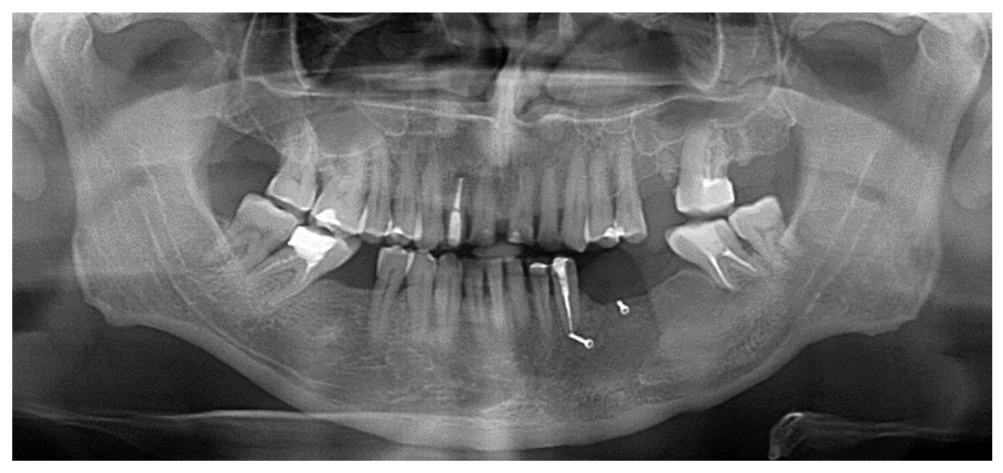

Пациент И., 58 лет, обратился в специализированное отделение многопрофильного стационара с жалобами на подвижность зубов нижней челюсти слева, онемение области левого угла рта. При проведении компьютерной томографии обнаружена киста нижней челюсти с деструктирующим ростом в проекции зубов 3.3–3.7 (рис. 1).

Рис. 1. Ортопантомограмма пациента И., 58 лет, исходная клиническая картина. / Fig. 1. Orthopantomogram of patient I., 58 years old, initial clinical picture.

Клинический диагноз: радикулярная киста нижней челюсти от зубов 3.3, 3.4. Вид полости рта до начала лечения и его этапы представлены на рис. 2.